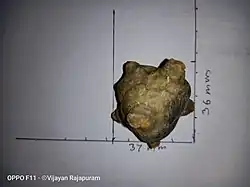

| A bladder stone removed from a patient. | |